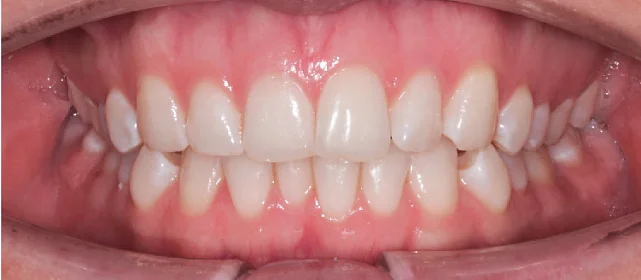

Результат

Зубы выровнены, скученность устранена, линия смыкания нормализована. Установлены несъёмные ретейнеры на обе челюсти, сняты слепки для ретенционных кап.

Решение: Поставили элайнеры Click на обе челюсти. Начали с 32 кап, но случай потребовал три дозаказа: 30, 10 и 10 кап — итого 82 капы за 30 месяцев. Количество дозаказов объясняется и сложностью случая (скученность плюс деформация кривой Шпее), и тем, что контрольные визиты были реже обычного из-за проживания за границей. Тем не менее результат достигнут: зубы ровные, смыкание в норме. На ретенцию пациентка приехала отдельно — зафиксировали ретейнеры на обе челюсти, сняли слепки для ретенционных кап.

Я живу не в России, поэтому прилетать часто не получалось. Врач это учла и выстроила лечение так, чтобы между визитами проходило больше времени. Дозаказов было три — каждый раз ждала новые капы и начинала заново. Это растягивает процесс, но я понимала, что мой случай непростой. Зато на ретенцию прилетела и увидела финальный результат — зубы ровные, кайф.